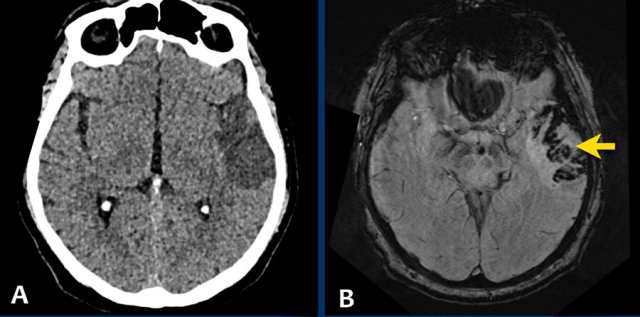

This patient was submitted to the stroke unit with a recent infarct in the left MCA territory.

Due to delay in presentation outside the thrombolytic window, no thrombolytic therapy was given.

A follow-up NECT (image A) was ordered because of clinically deterioration and showed a well demarcated hypodense area in the left MCA territory. In the hypodense area, very small subtle hyperdens foci were depicted.

MRI several hours later the same day showed foci of hemorrhage (arrow) indicating petechial hemorrhagic transformation of the ischemic infarct.